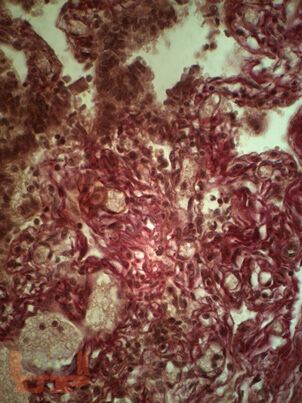

В монографии изложены данные отечественных и зарубежных авторов, результаты собственных исследований, посвященных современным проблемам воспалительных заболеваний органов малого таза (ВЗОМТ). Особое внимание уделено комплексному методу лечения и реабилитации осложненных форм ВЗОМТ с включением квантовой терапии. В монографии представлены собственные результаты клинико-лабораторных, инструментальных методов обследования пациенток с гнойными тубоовариальными образованиями, а также результаты применения квантовой терапии.